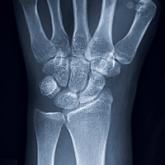

While driving through an intersection, this 35-year-old woman collided with another vehicle. Her only complaint on arrival at the emergency...